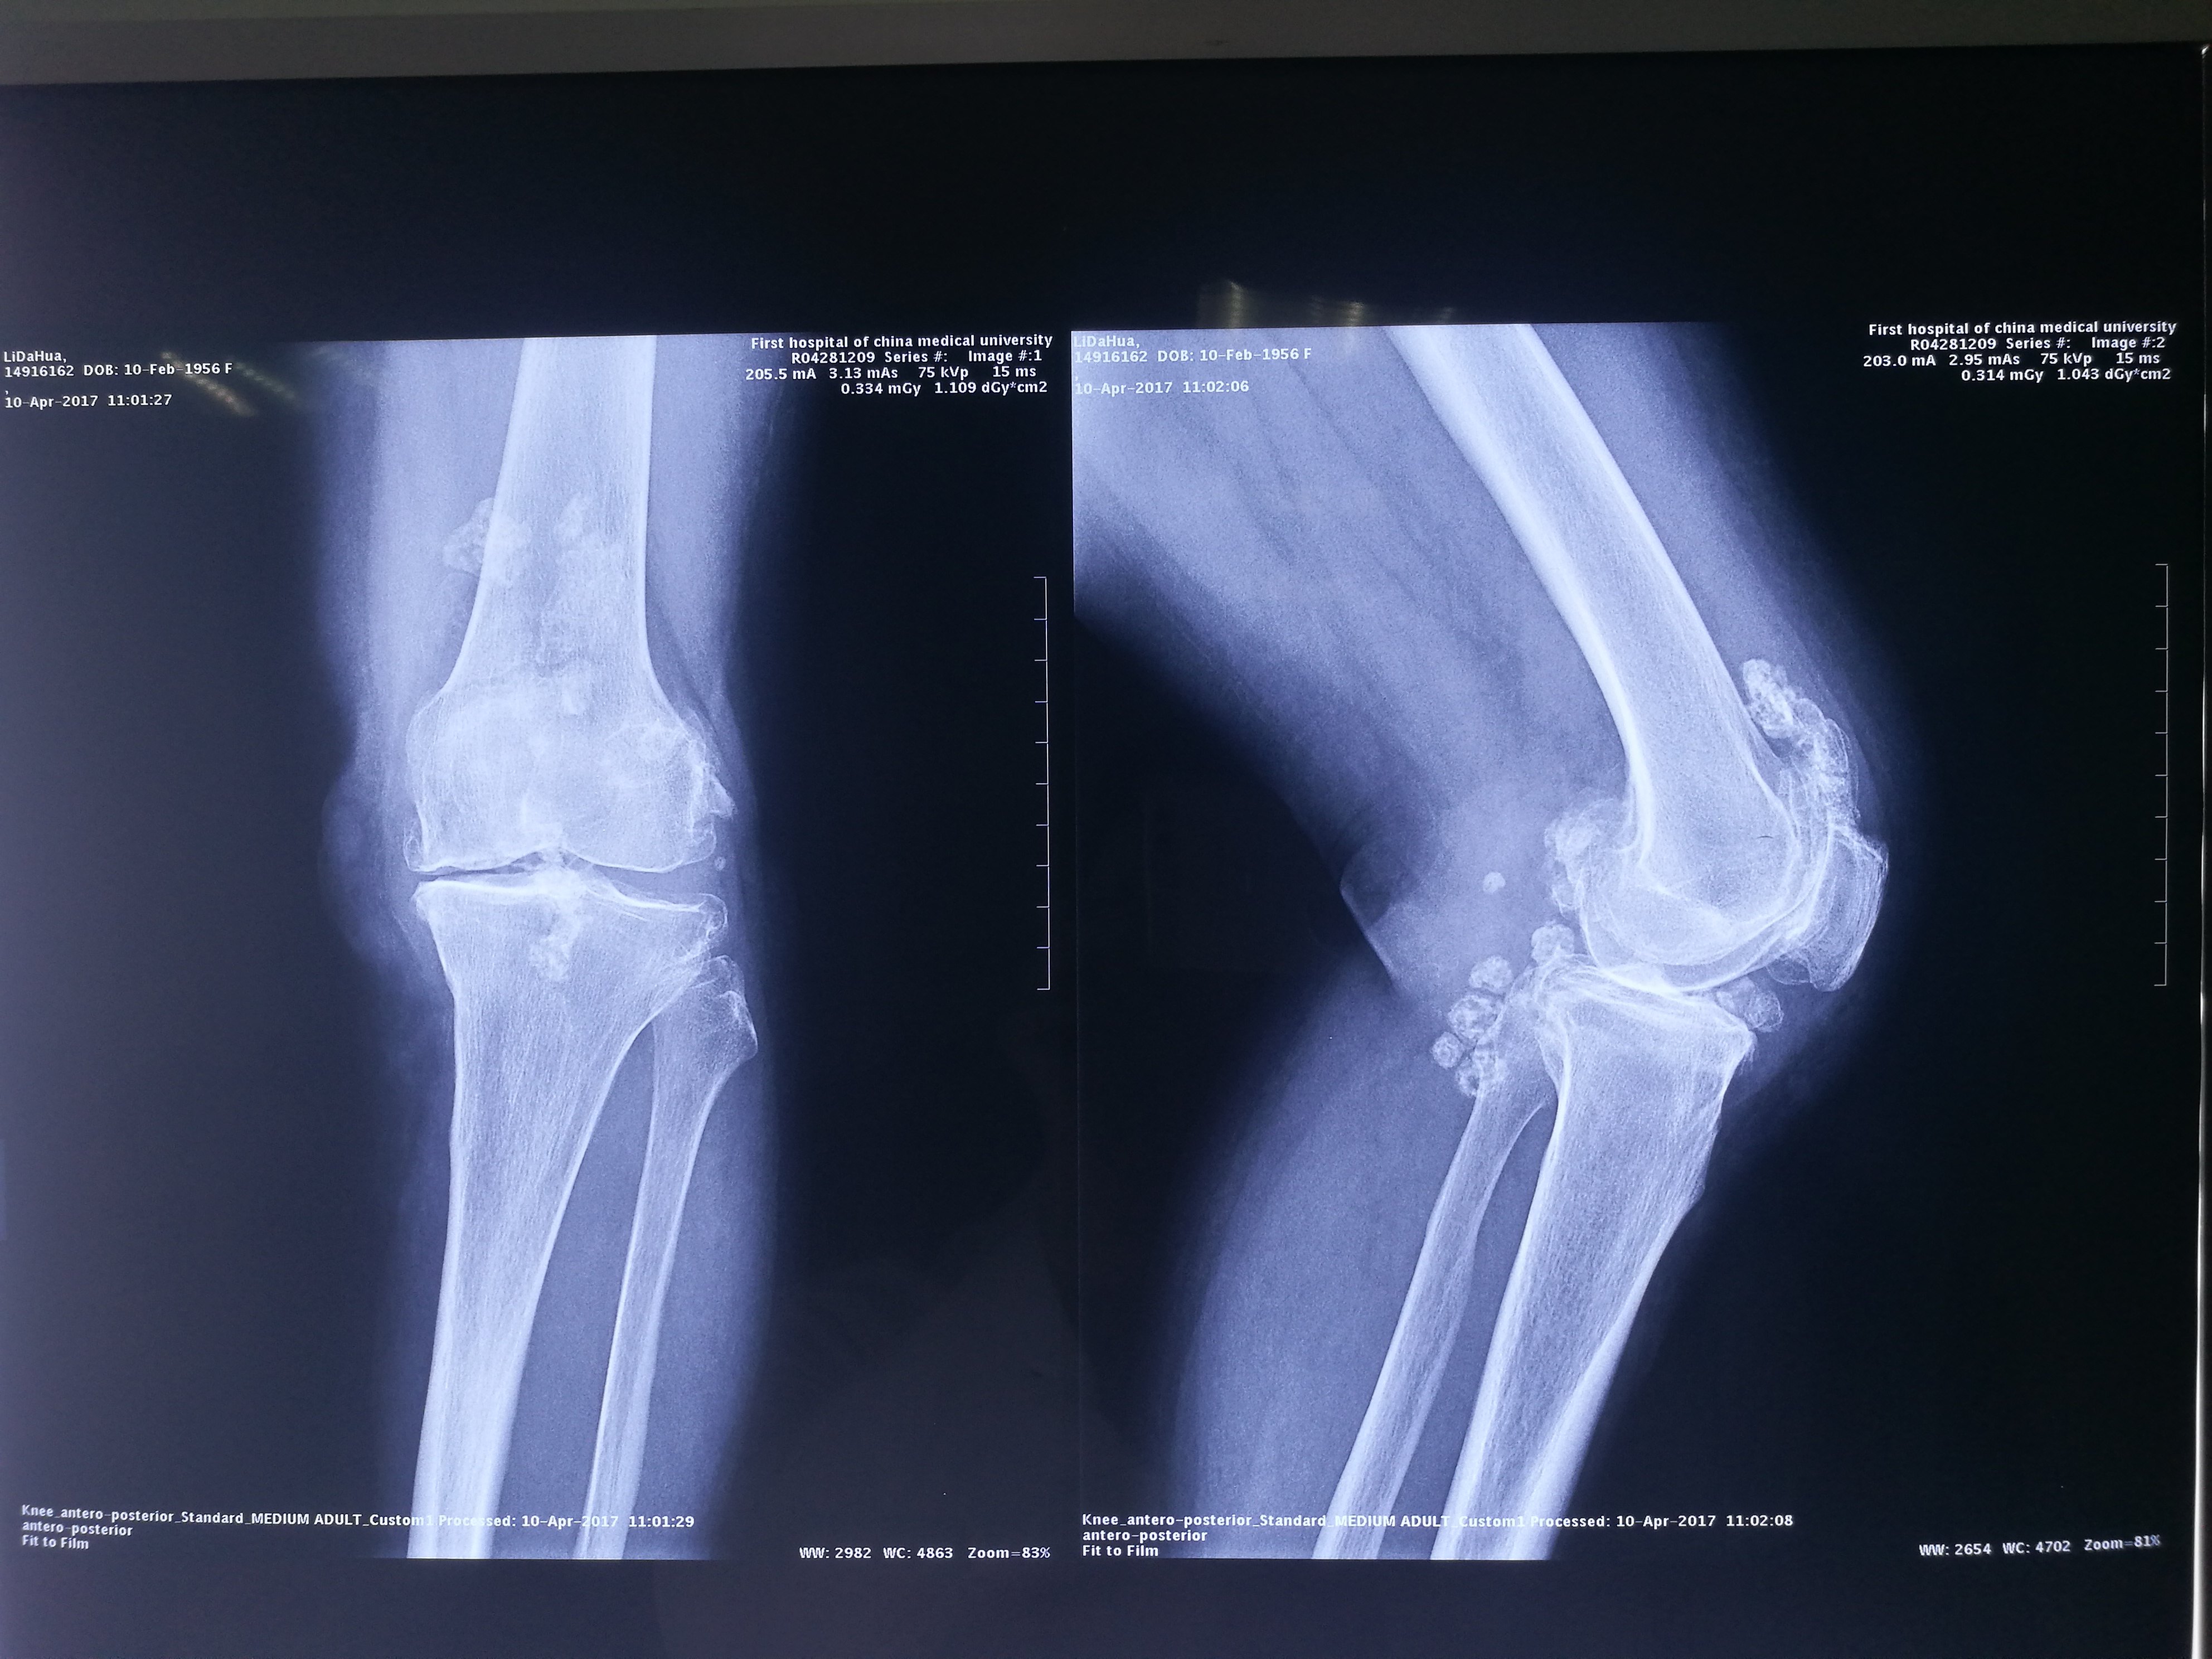

61岁女性,膝关节滑膜软骨瘤病,关节炎,全膝关节置换术